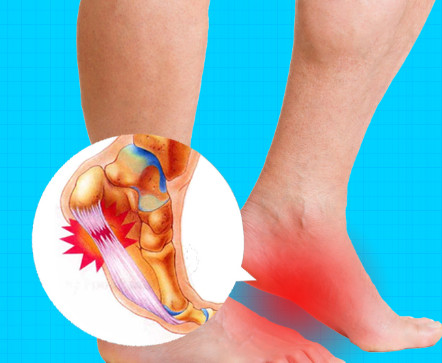

족저근막염 원인

1. 무리한 걷기나 달리기

우리 발에는 미세한 근육들이 많은데, 무리하게 걷거나 뛰게 되면 그 근육들이 미세하게 파괴 된다고 합니다. 이렇게 되면 신체는 다시 그 근육들을 회복시키려고 하는데, 만약 이 회복기에 또다시 무리하게 움직이게 되면 염증이 발생하면서 통증이 느껴지는 것입니다.

2. 비만

여성분들의 경우 결혼이나 출산으로 인하여 갑자기 체중이 많이 늘어나면서 서있을 때 근육이 버티지 못하여 발바닥 근육에 염증이 발생하게 됩니다.